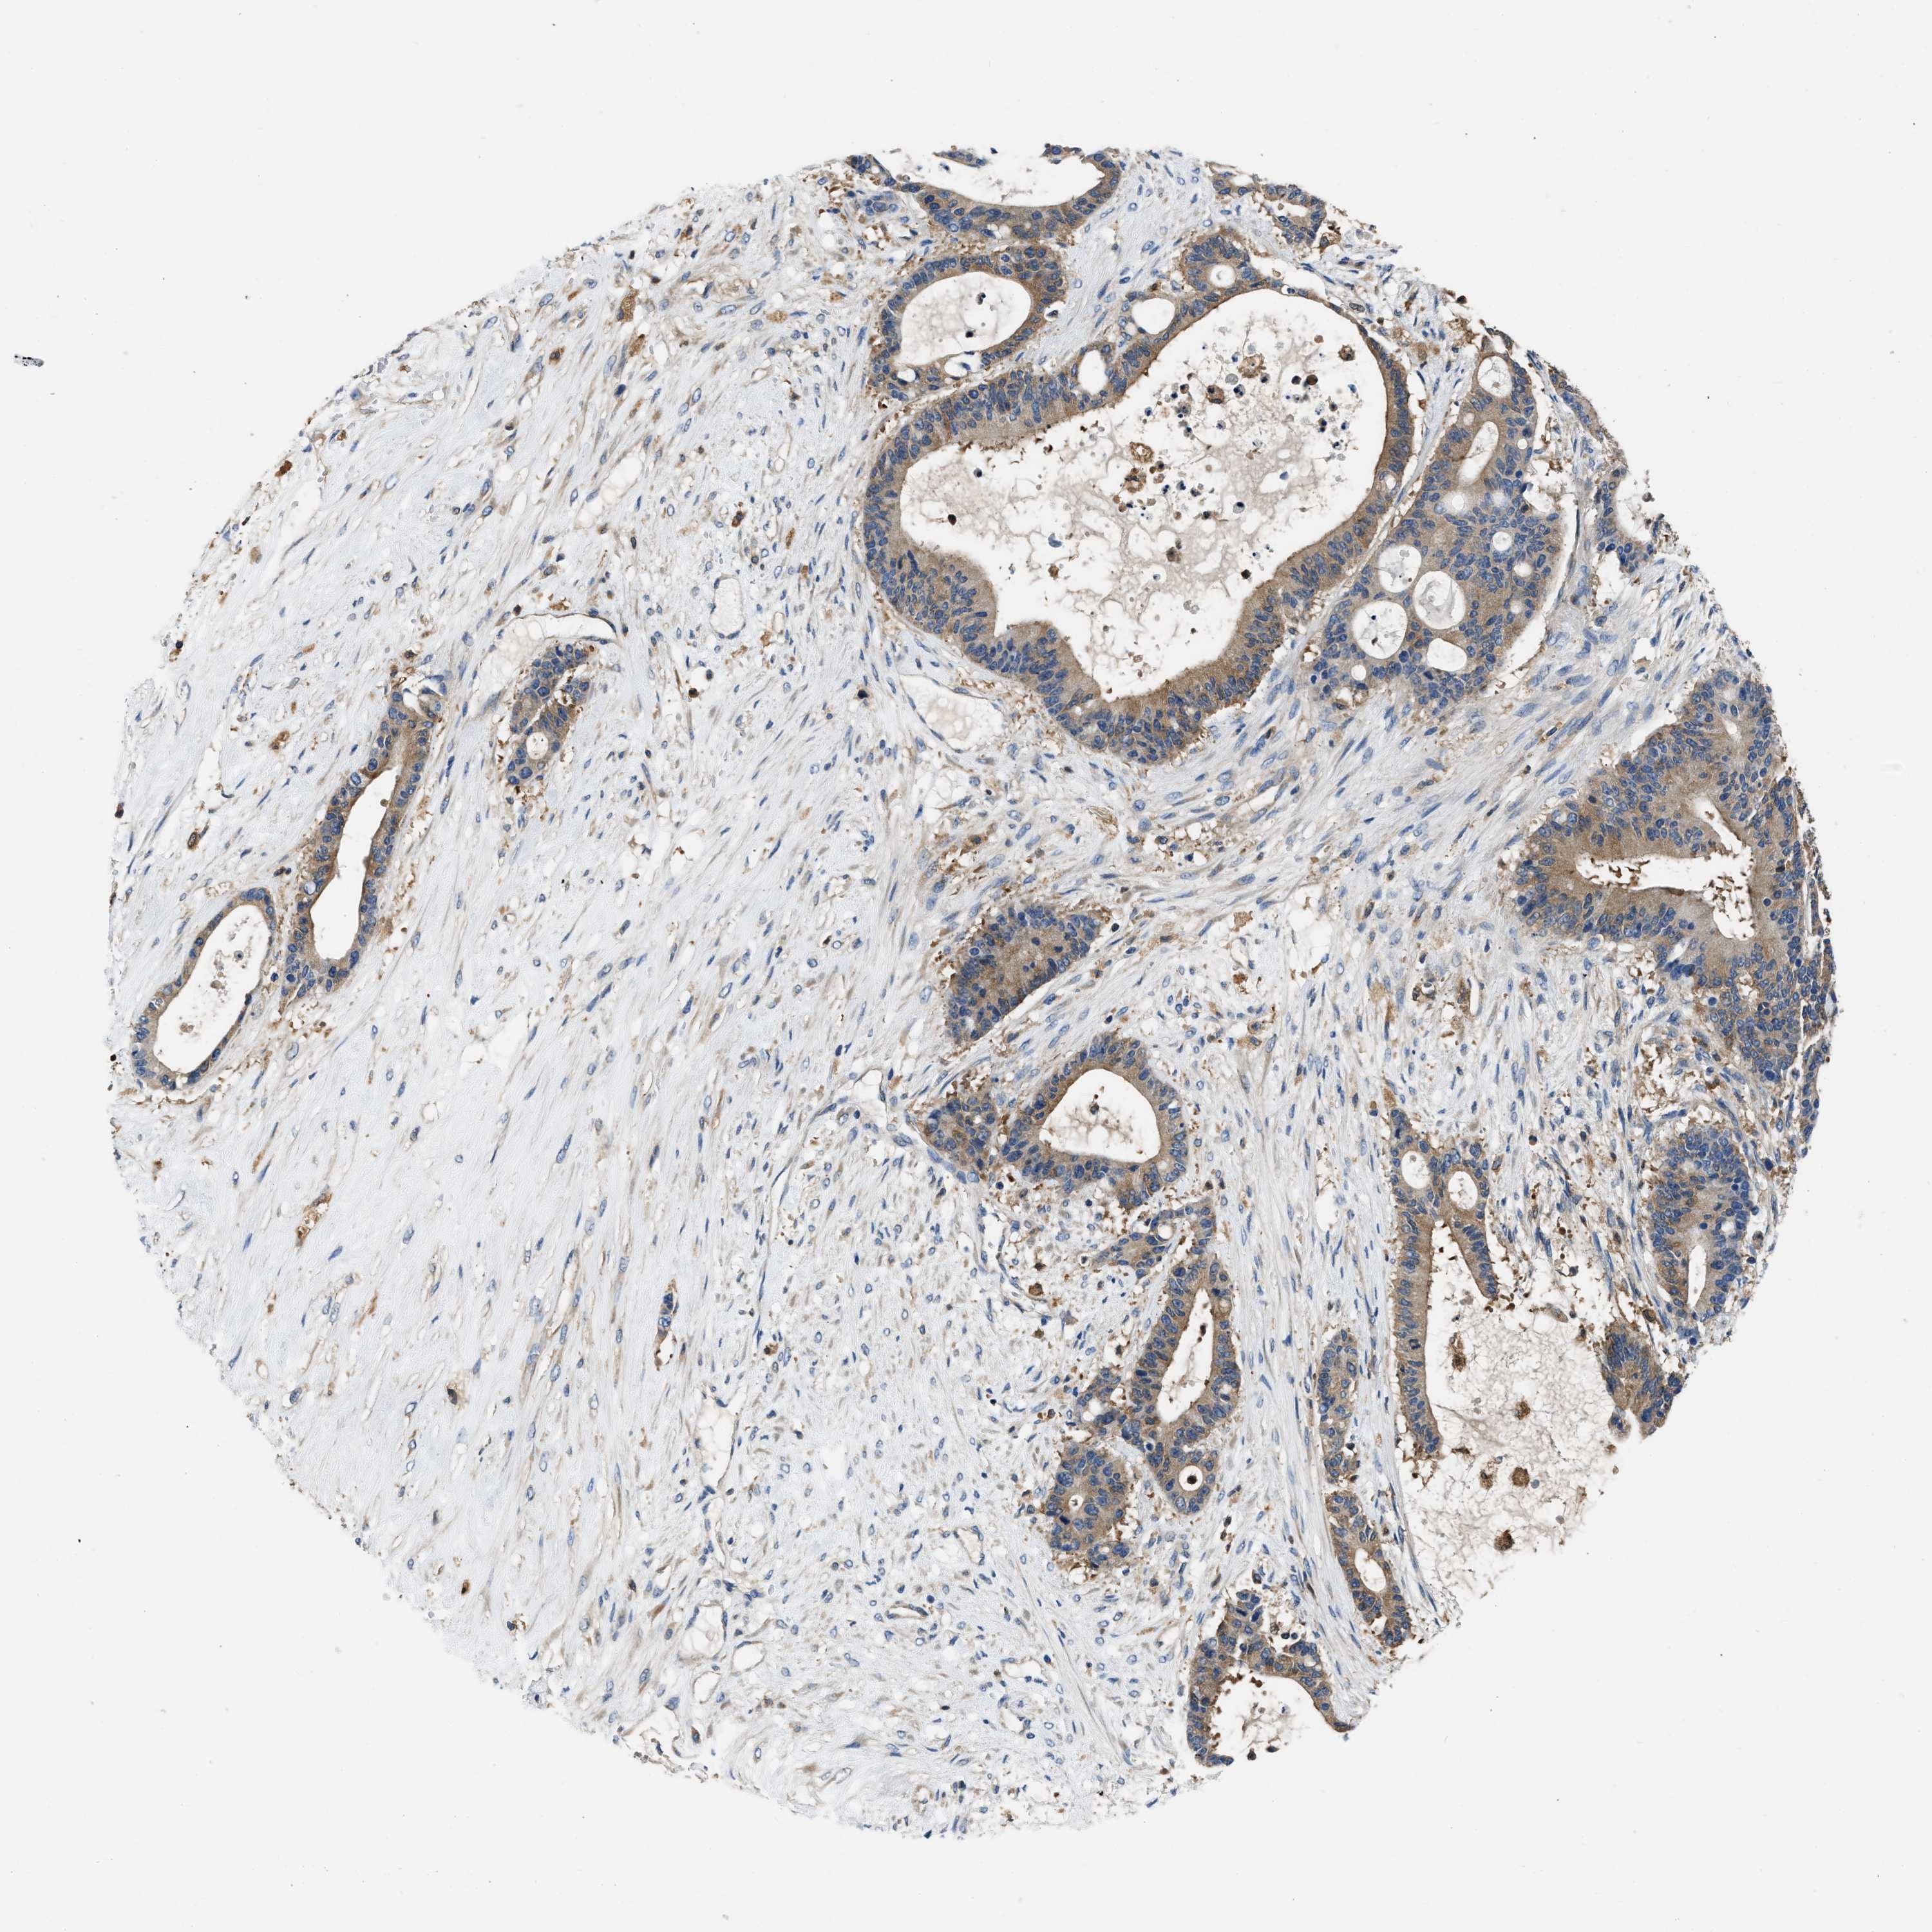

LIVER CANCER - Protein expressioni

A mouse-over function shows sample information and annotation data. Click on an image to view it in a full screen mode. Samples can be filtered based on level of antibody staining by selecting one or several of the following categories: high, medium, low and not detected. The assay and annotation is described here.

Note that samples used for immunohistochemistry by the Human Protein Atlas do not correspond to samples in the TCGA dataset.

Antibody stainingi

Antibody staining in the annotated cell types in the current human tissue is reported as not detected, low, medium, or high, based on conventional immunohistochemistry profiling in selected tissues. This score is based on the combination of the staining intensity and fraction of stained cells.

Each image is clickable and will lead to virtual microscopy that enables deeper exploration of all samples and also displays staining intensity scores, fraction scores and subcellular localization as well as patient and tissue information for each sample.

Antibody HPA029501

Antibody CAB019421

Staining

Cholangiocarcinoma

Carcinoma, Hepatocellular, NOS